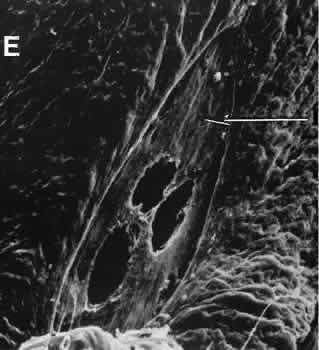

Wound healing of the posterior uveal tract follows the general principles for healing of vascularized tissue. The iris, however, heals differently. When the iris wound is perpendicular to its circumferential ridges, such as in a typical peripheral iridectomy or iridotomy, the cut edges pull apart. Granulation tissue does not form to close iridectomy incisions probably because of the inhibitory effect of the aqueous flowing through the opening of these small incisions. Iridotomies created by argon laser (Fig. 10) may be anatomically closed by apparent migration of iris pigment epithelium.36,37

Fig. 10. Scanning electron micrograph of the posterior surface of the iris in a case of angle closure glaucoma treated with argon laser iridotomy. Centrally, there are three areas of penetration of iris tissue. Iris pigment epithelium has been lost for a considerable distance from the actual opening (arrow). Normal iris pigment epithelium is present peripherally.